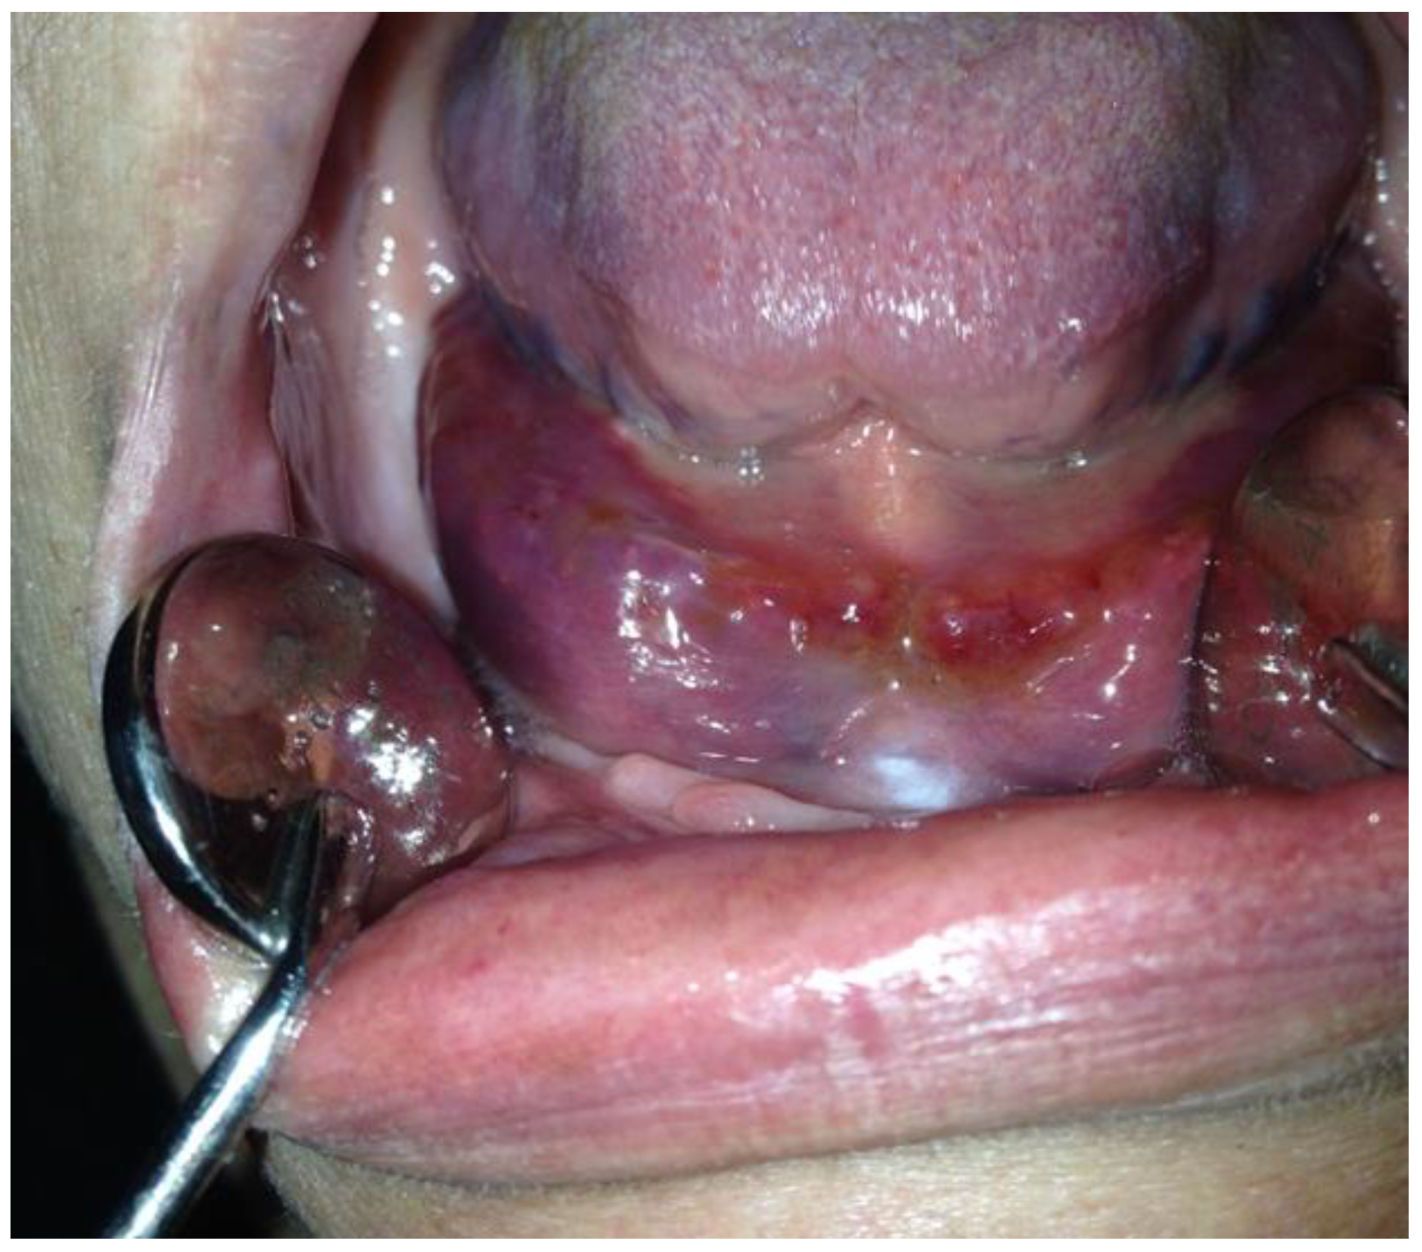

Oral Manifestations of Vitamin C Deficiency